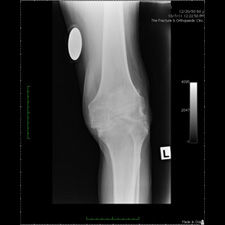

Patient seen with Bilateral Knee Pain and had been unable to walk for two (2) years.

On clinical and radiological examination, he was assessed as having Severe Primary Osteoarthritis of both knees.